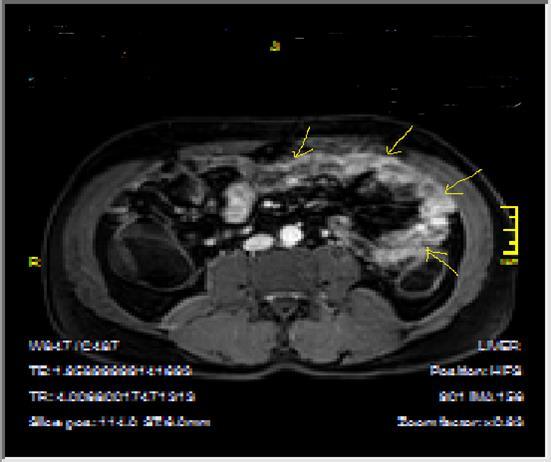

Figure 5a.Enhancing bowel segments due to Crohn’s disease, on T1W post-contrast axial image, luminal enhancement is predominant, shown at 62 years old female with mild disease status.

Figure 5b.İrregular bowel wall and luminal enhancement of ileum, with loss of valvula conniventes on T1W coronal post-contrast sequence, seen on 26 years old male with moderate inflammatory bowel disease.

Figure 6a.Diffuse homogeneous contrast enhancement on the bowel wall and mucosa due to Crohn’s disease, seen at T1W post-contrast axial image, indicated at 23 years old male with mild disease status.

Figure 6b.Heterogeneous bowel wall and mucosa involvement with collaborating skip lesions, specific for Crohn’s disease, predominant in ileum and terminal ileum which are shown at T2W coronal sequence after OCA, regarded at 39 years old female with severe disease.